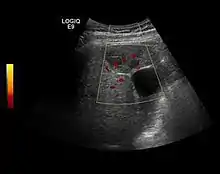

Hepatocellular carcinoma (HCC)

It is the most common liver malignancy. It develops secondary to cirrhosis therefore, ultrasound examination every 6 months combined with alpha fetoprotein (AFP) determination is an effective method for early detection and treatment monitoring for this type of tumor . Clinically, HCC overlaps with advanced liver cirrhosis (long evolution, repeated vascular and parenchymal decompensation, sometimes bleeding due to variceal leakage) in addition to accelerated weight loss in the recent past and lack of appetite.

HCC appearance on 2D ultrasound is that of a solid tumor, with imprecise delineation, with heterogeneous structure, uni- or multilocular (encephaloid form). An "infiltrative" type is also described which is difficult to discriminate from liver nodular reconstruction in cirrhosis. Typically HCC invades liver vessels, primarily the portal veins but also the hepatic veins . Doppler examination detects a high speed arterial flow and low impedance index (correlated with described changes in tumor angiogenesis). The spatial distribution of the vessels is irregular, disordered. CEUS examination shows hyperenhancement of the lesion during the arterial phase. During the portal venous phase there is a specific "wash out" of ultrasound contrast agent (UCA) and the tumor appears hypoechoic during the late phase. Poorly differentiated tumors may have a stronger wash out leading to an isoechoic appearance to the liver parenchyma during portal venous phase. This appearance was found in approx. 30% of cases. The described changes have diagnostic value in liver nodules larger than 2 cm.